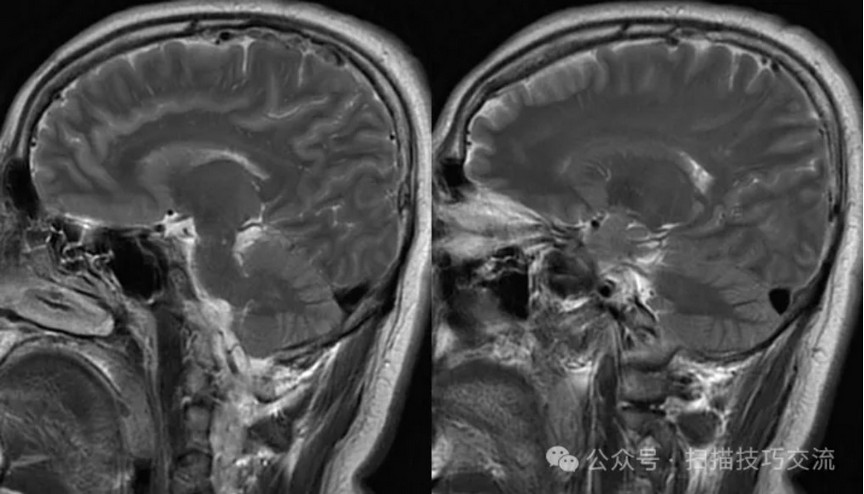

•男性,29岁,已婚 •头痛伴头晕恶心呕吐20余天 •现病史:患者于20天前,熬夜饮酒后出现头痛,为胀痛,头痛剧烈,伴头晕恶心呕吐。就诊于当地医院,未作出明确诊断。现症状有所缓解,于平卧位时无明显不适,坐位或直立式上述症状加重。急诊以“头痛”收入卒中中心。病程中无视物模糊,无饮水呛咳,无吞咽困难,无抽搐发作等症状。自发病以来睡眠欠佳,近3日未进食,二便正常。近期体重未见明显变化。 •既往史:平素健康,过敏史或不良反应药物反应史无。外伤史无。手术史无。传染病史无。预防接种史无。其它无。

•汗腺分泌:正常,皮肤划痕正常反应。 •尿便障碍:无。性功能障碍无。 •专科情况:正常。不逐一罗列。 •辅助检查:01-05颅脑CT提示:1,上矢状窦、双侧横窦密度较高,请结合临床,必要时进一步检查;2,双侧脑室后角可疑稍高密度影,右顶叶局部脑沟密度可疑增高,建议进一步检查。 •初步诊断:静脉窦血栓

临床申请:颅脑平扫,静脉成像,磁敏感成像,颅内静脉血管黑血成像。